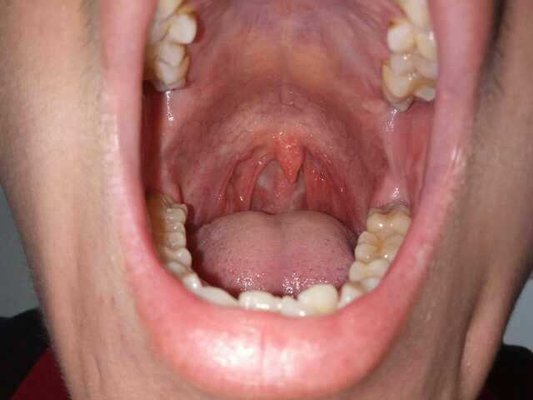

Cough with weight loss is pulmonary tuberculosis (PTB) is a pulmonary infectious disease caused by Mycobacterium tuberculosis. It is one of the symptoms of diseases that seriously threaten human health. What are the causes of cough with weight loss? Let's talk about it now.

After the initial pulmonary infection (usually in children), the bacteria are carried by phagocytes to the hilar lymph nodes (lymphadenopathy) and can spread throughout the body (occult bacteremia). At this time, if the body has low immunity, it may develop into primary progressive tuberculosis, but in adults (who have had mild tuberculosis infection or had been inoculated with BCG vaccine in childhood), the body has certain immunity, and then reinfection occurs Most of them did not cause local lymphadenopathy or systemic spread, but had severe tissue reaction in the reinfected area. The lesions were mostly exudative or even caseous necrosis and dissolved to form cavities.

After entering the 1990s, tuberculosis, which had been under control, appeared a widespread epidemic trend in the world. The fight against tuberculosis has entered a new era. It is more difficult to treat drug-resistant tuberculosis, so it is very important to prevent tuberculosis. When you have unexplained low fever, emaciation, fatigue, cough, night sweats, and no other causes, you should quickly go to the hospital for examination and diagnosis. Under the guidance of specialists, regular, full course of medication, course of treatment should not be less than half a year, patients should have enough patience. Rest, adequate nutrition, proper outdoor activities, and enhancing systemic resistance are still the important conditions for overcoming diseases. It is very important to protect the health of family members and collective population, especially children.